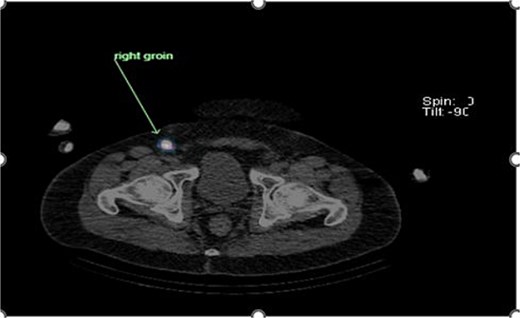

Preoperative lymphoscintigraphy was performed to detect the sentinel lymph node (Fig. 1), expecting it to be in the right inguinal region (Fig. 2). However, drainage to both the right axillary (Fig. 3) and inguinal areas was demonstrated. During surgery, a gamma camera confirmed drainage to both regions (Fig. 4). Blue dye was injected around the previous scar, and sentinel nodes were dissected guided by both blue dye and gamma camera for histopathology.

Intraoperative gamma probe confirming dual drainage to axillary and inguinal regions.

Histology showed no residual malignancy in the re-excision specimen. The right axillary node showed involvement by metastatic melanoma, while the groin lymph node was negative.